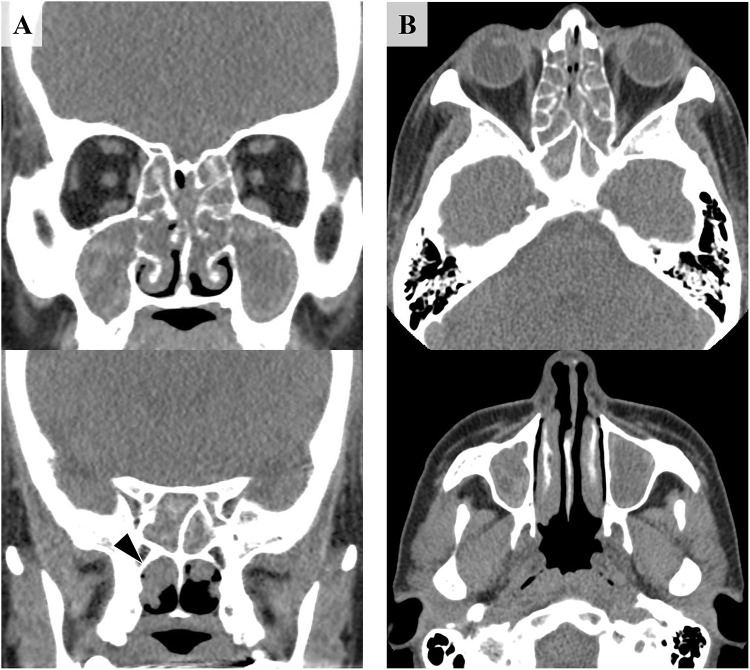

Case study: A 48-year-old female with severe eosinophilic rhinosinusitis and asthma, increased blood eosinophils (2098/μL) and myeloperoxidase-specific antineutrophil cytoplasmic antibody (MPO-ANCA) (46.1 U/mL) without vasculitic symptoms, developed systemic symptoms, including fever, arthralgia, and peripheral neuropathy immediately after dupilumab administration.